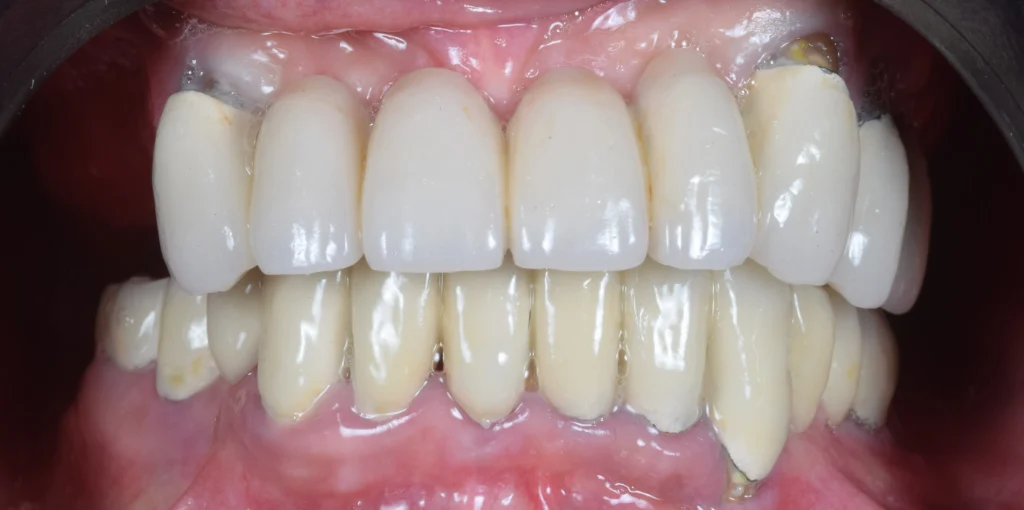

After the examination and all the analysis, the therapy plan consisted of a full mouth reconstruction with dental implants.  All the teeth were removed and the implants were placed immediately. The patient was provided with temporary teeth during the healing period.

After 6 months of osseointegration of the dental implants, we provided a new beautiful smile with a hybrid construction, zirconia on a titanium bar.